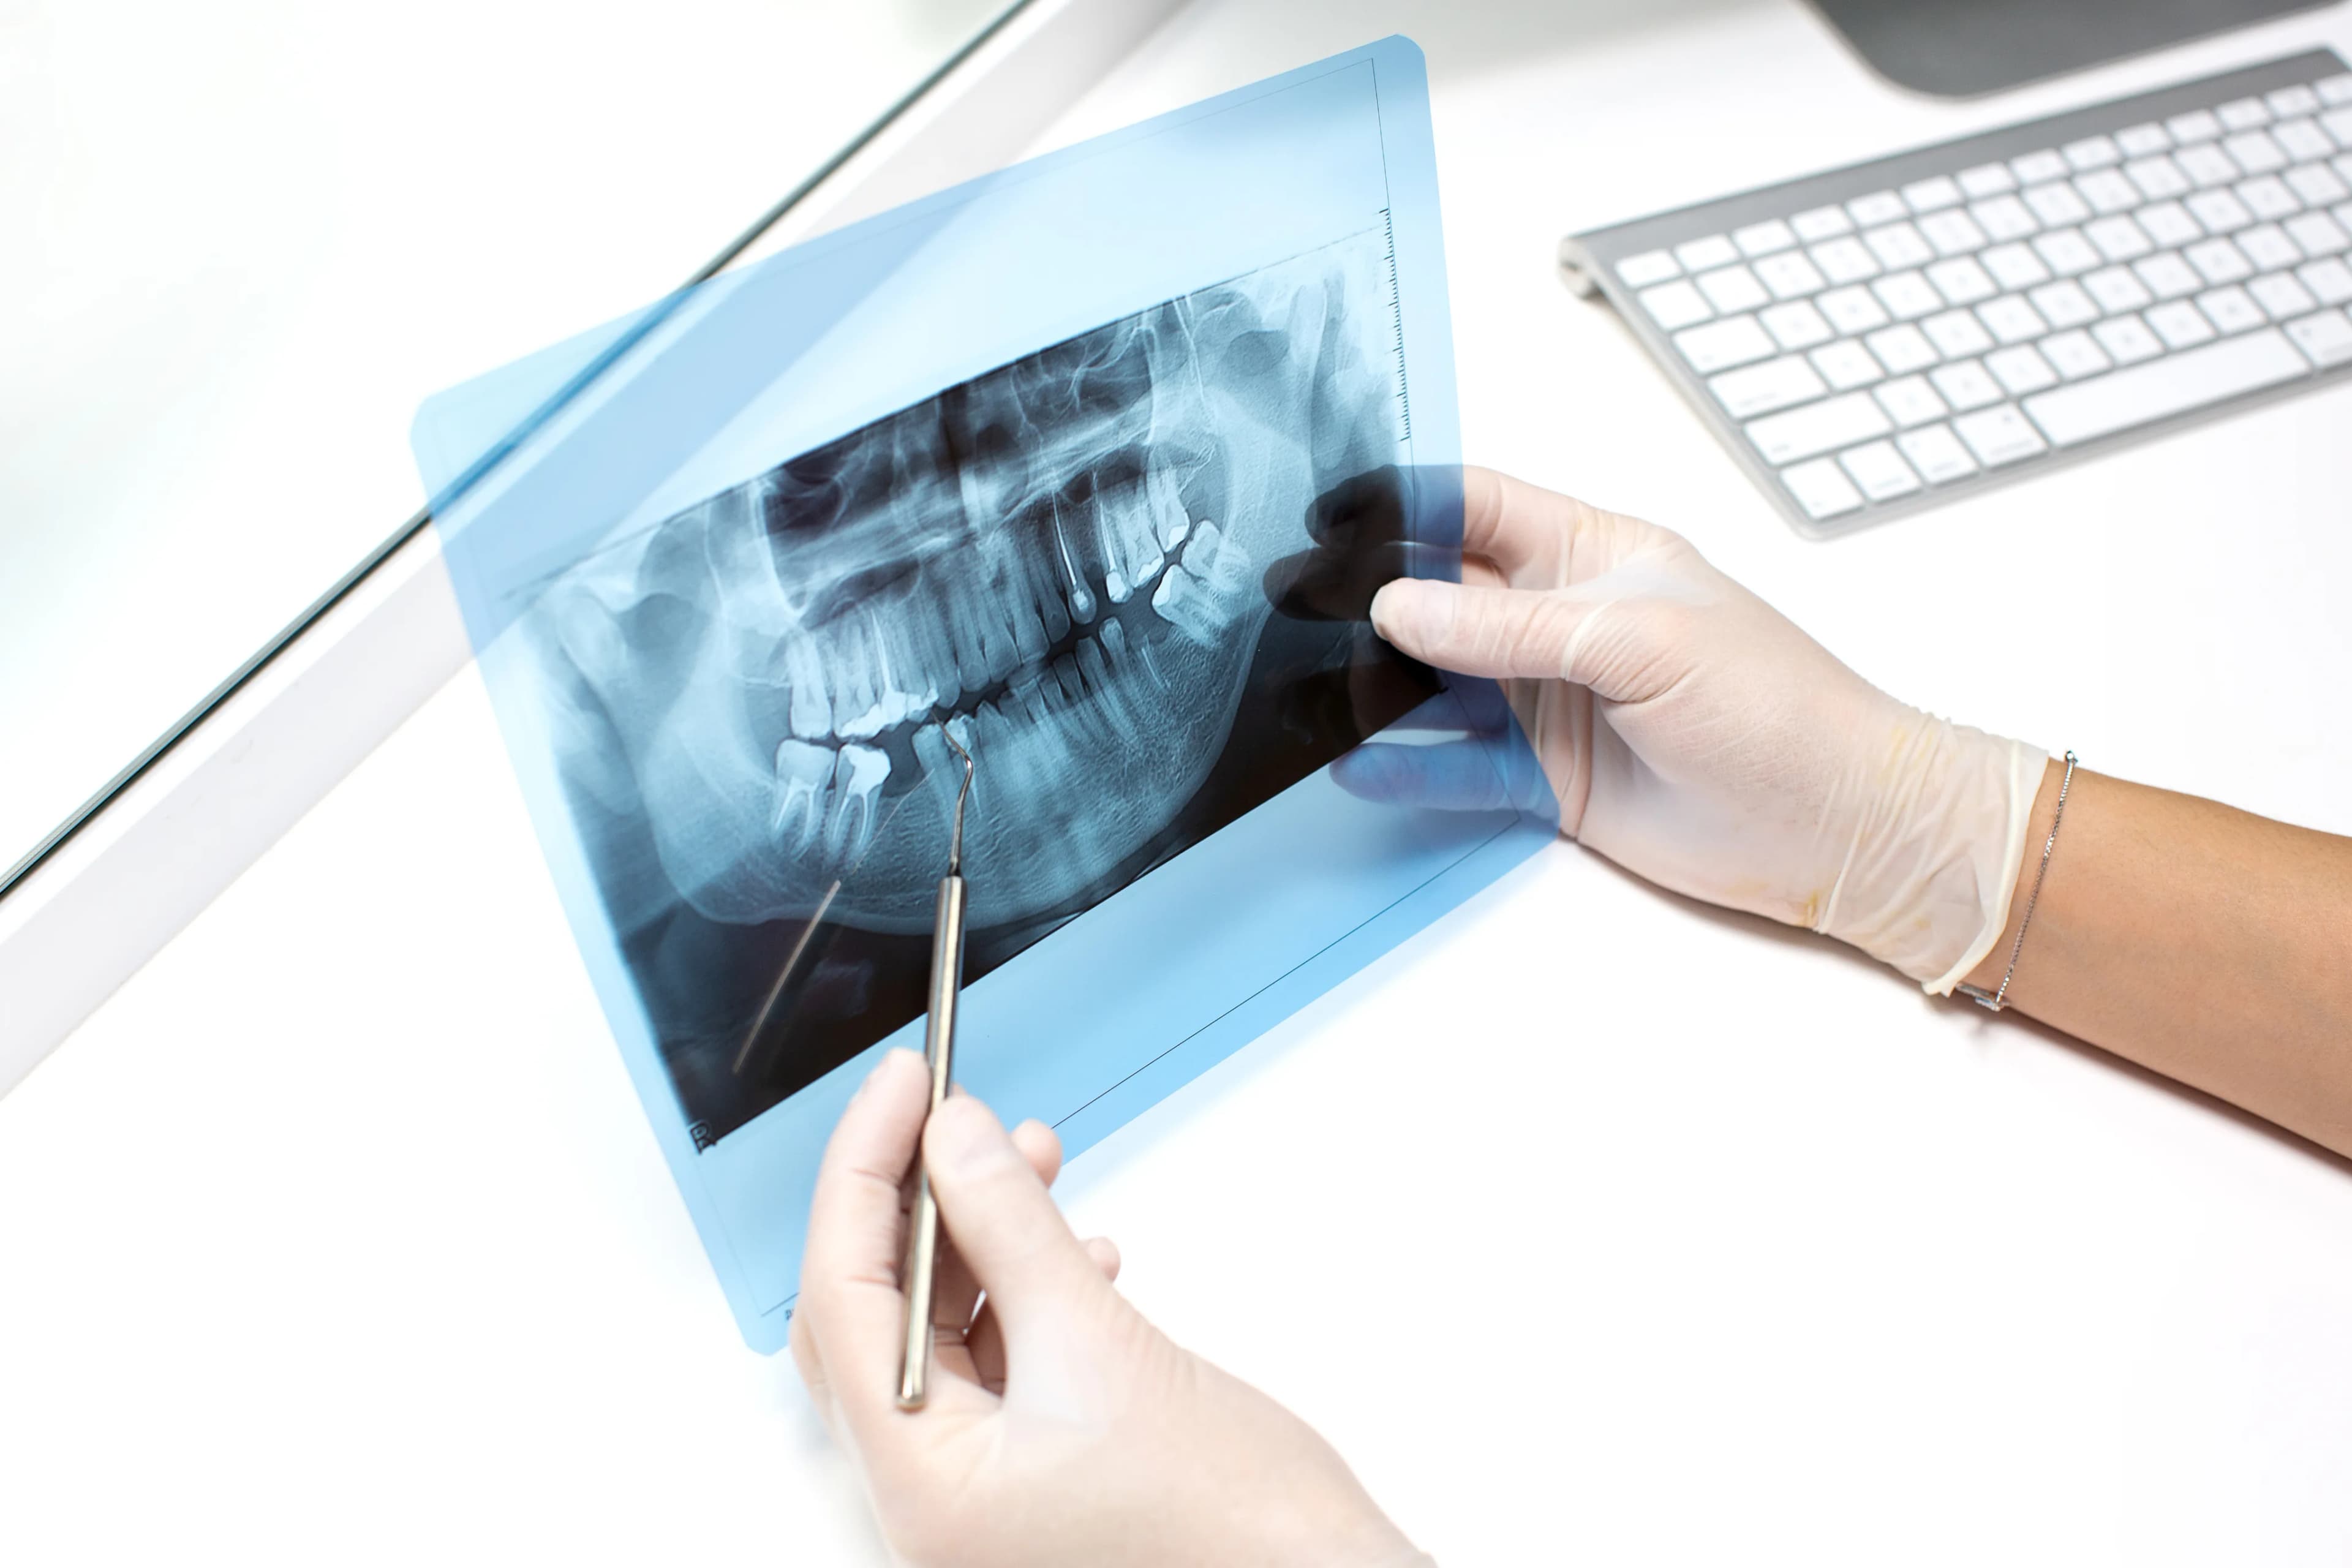

Professional online interpretation and reporting of your dental radiology studies by expert radiologists, ensuring comprehensive and accurate results.

Dental tele-reporting, as offered by Vi-Scan Diagnostics, is a professional online service for the interpretation and reporting of dental radiology studies. This service provides comprehensive and very detailed reports, prepared by expert dental radiologists who utilize advanced technology and tools.

Dental diagnostics services provide essential assessments to identify oral health issues. These services include comprehensive examinations, X-rays, and advanced imaging techniques to ensure accurate diagnosis and effective treatment planning. Regular check-ups help in early detection of problems, allowing for timely interventions and better overall dental health.